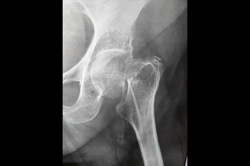

Neck Femur Fracture